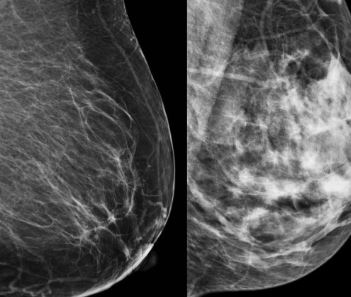

유방암은 조기에 발견할수록 치료가 쉽고, 생존율도 높아져요. 정기적인 자가 검진과 함께 전문적인 검진을 통해 유방암을 조기에 발견할 수 있어요. 특히, 40세 이상의 여성은 매년 유방 촬영술(맘모그램)을 받는 것이 권장돼요.

유방암의 생존율을 높이기 위해 가장 중요한 것은 정기 검진이에요. 정기적인 유방 촬영술(맘모그램)과 유방 초음파 검사를 통해 유방암을 조기에 발견할 수 있어요. 조기 발견 시 치료 성공률이 높아져요.

4.2 정기적인 유방 촬영술(맘모그램)

유방 촬영술(맘모그램)은 유방암 조기 발견을 위한 가장 중요한 검사 중 하나예요. 특히, 40세 이상의 여성은 매년 정기적으로 맘모그램을 받는 것이 권장돼요. 이 검사는 유방암 초기 단계에서 발견할 수 있는 유용한 방법이에요.